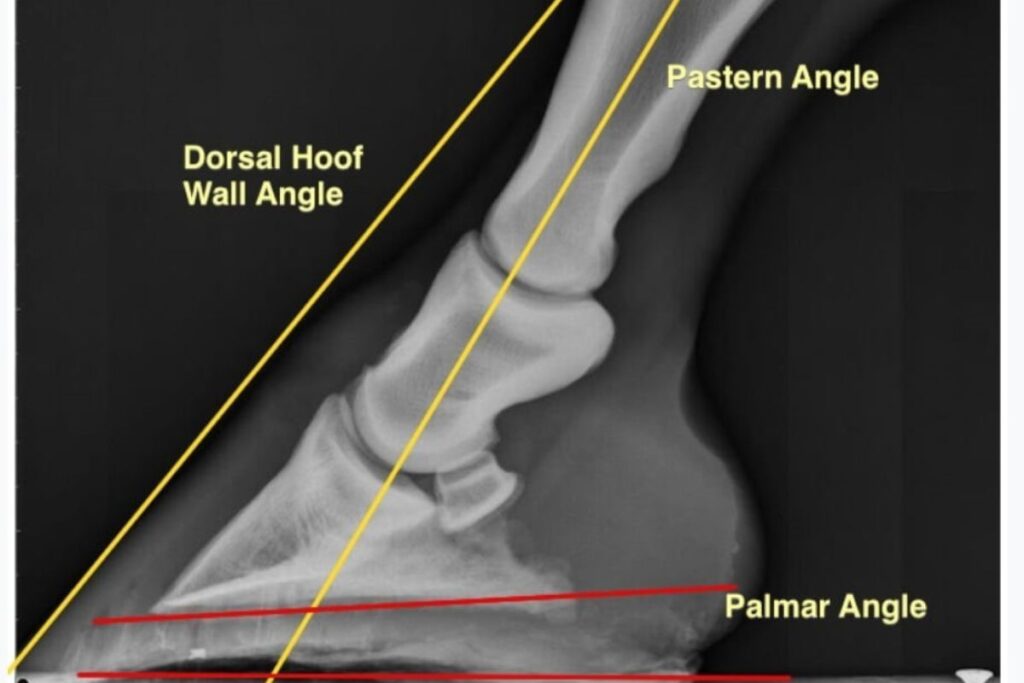

During the trial they were all shoed every sixth week. All hoofs were measured from different angles both lateral (outside measurements) and dorsal (front of the hoofs). Hereafter, the positions of legs and pressure was calculated after shoeing.

Before trimming the hoofs, scientists discovered that the dorsal angle was smaller. This can lead to more pressure on the heel because the weight of the horse is placed more at the back.

Increased pressure on the back of the hoof also creates a higher risk of ligament injuries. After trimming the hoofs it was clear that the position was more vertical and this affected the rest of the hoof and the leg positively.